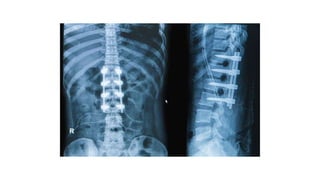

Surgical correction of the misplaced

vertebra is required when the bone

has slipped so far down that your

spine doesn’t respond to nonsurgical

therapies. Surgery is also required if

the bones of your spine are pressing

on your nerves

Surgery can usually correct the appearance of the

back and may help to relieve pain but it carries quite a

high risk of complications. Surgery is only

recommended for more severe cases of kyphosis,

where it's felt the potential benefits of surgery outweigh

the risks.